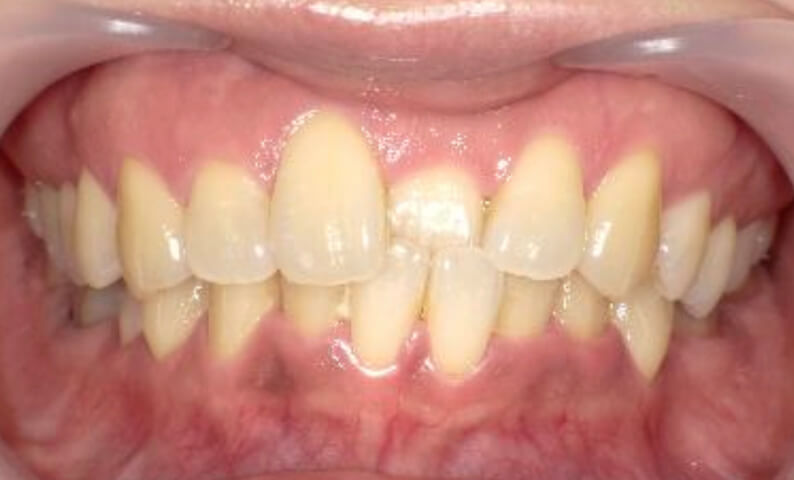

症例_022 上下顎の部分矯正

治療期間:9ヶ月金額:51万円+税女性前歯のガタガタ八重歯

| Before | After |